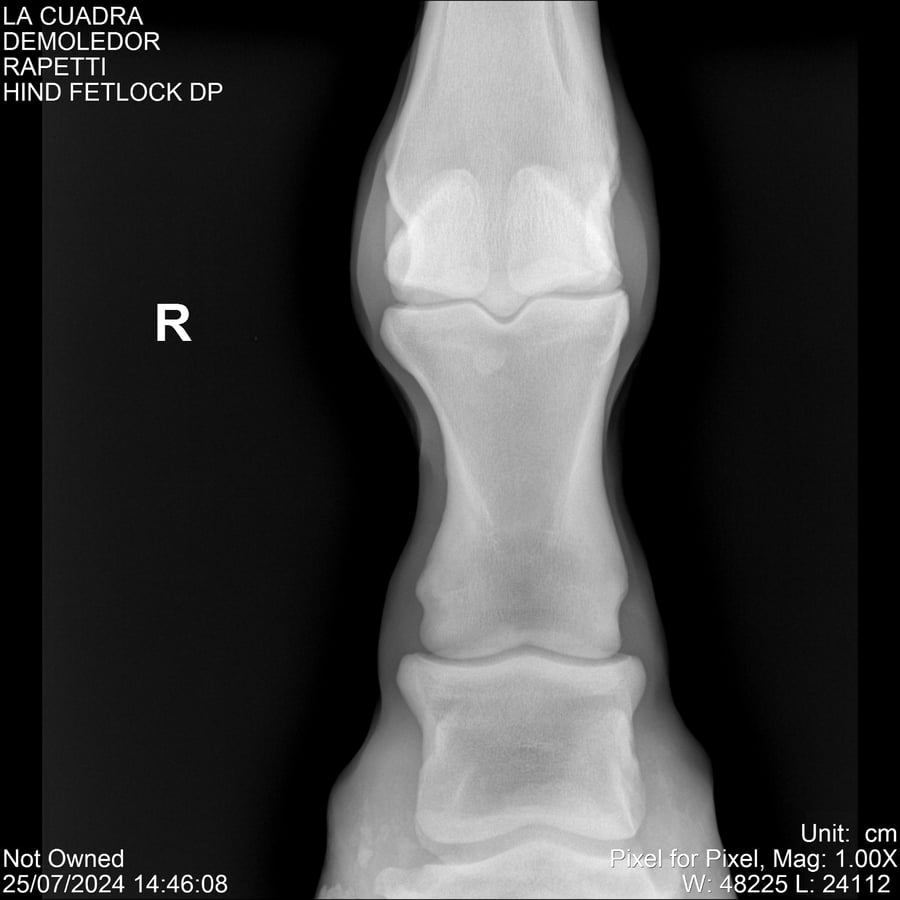

LOTE 14, DEMOLEDOR 🔥 🔥 🔥 Lote Anterior Volver al remate Lote Siguiente Ficha Contacto Montevideo - Ficha del Lote Identificador: #284454 Categoría: Yeguarizos Montevideo - 89 Visualizaciones ClicData Contacto Empresa: Abelenda N. R., Walter Hugo Nombre*: Teléfono* : E-mail* : Mensaje Enviar Registrese gratis Este contenido Exclusivo está disponible sólo para usuarios registrados Ingresar